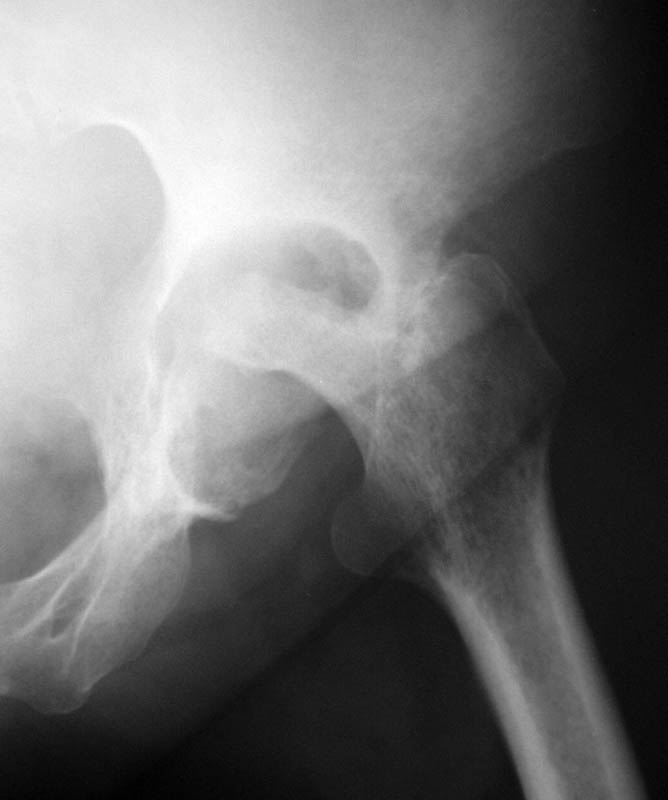

Женщина, 45 лет. В марте перенесла левосторонний коксит неизвестной этиологии. Специфику и онкологию исключили.

Интраартикулярных инъекций не было. Сейчас процесс клинически и рентгенологически - стабилизировался. Состояние вполне удовлетворительное.Предполагается тотальное эндопротезирование с пластикой полости аутокостью. Возможна ли бесцементная <чашка>? Заранее благодарю! С уважением,А.В.Владзимирский

Пртезирование через пол года после коксита закончившегося лизисом сустава, который на снимках выглядит как гнойный? Что значит неизвестной этиологии?

Уважаемый коллега! Последняя версия - мы пролистали ренгенологическую книженцию-так картинка вполне подходит под сустав Шарко (neuropatic joint ). В тазобедренном суставе патология редкая (но меткая). Ищите причину - варианты - нейросифилис, сирингомиелия, опухи спинного мозга (и выше тоже) компрессия спинного

мозга извне, рассеяный склероз, алкоголизм. А так-же : склеродерма ,Рейно,ревматоидный артрит, амилоидная инфильтрация нервов,и это не считая всяких менингеомиелоцеле,asymbolia,Riley-Day syndrom,и все возможные другие нейропатии. На данном этапе не спешите оперировать(протезирование протиопоказано при нейропатических суставах),проконсультируйтесь с классным невропатологом,сделайте МЯР головного озга и

весь позвоночник. И держите нас в курсе - случай крайне интересный :)